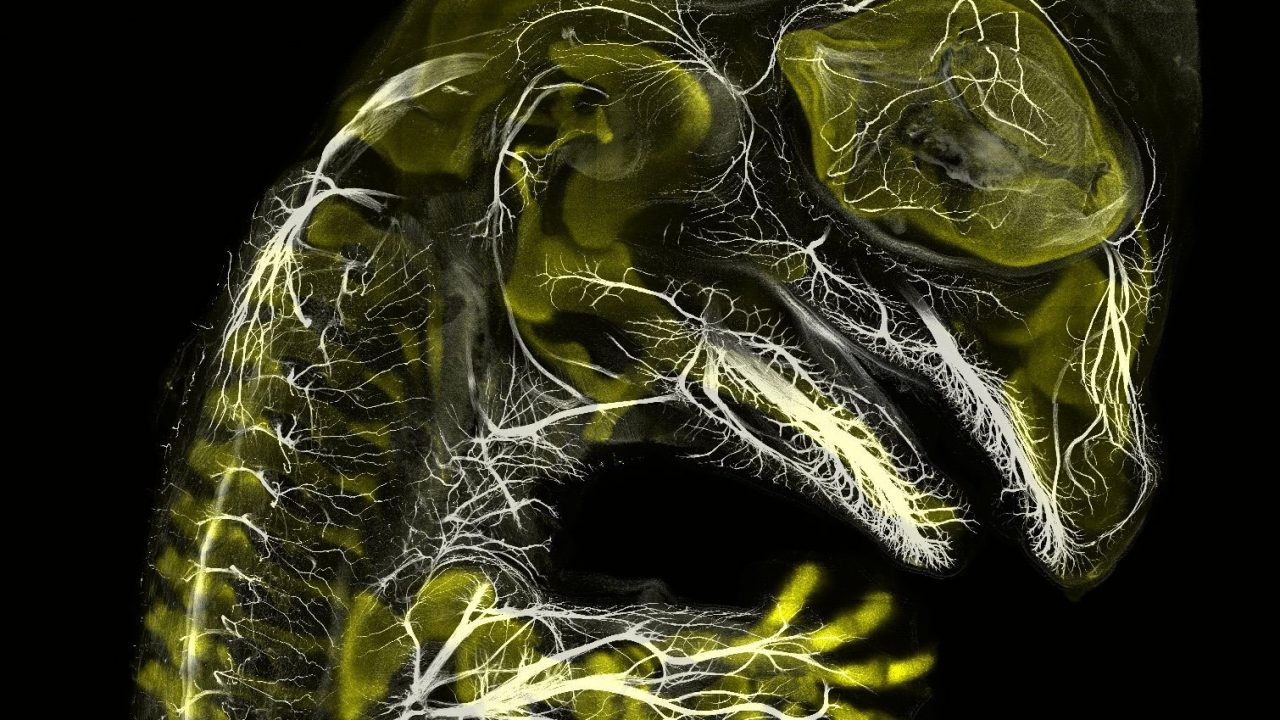

Se de smukke mikroskopiske videoer: Spirende polypper, musefostre og ...